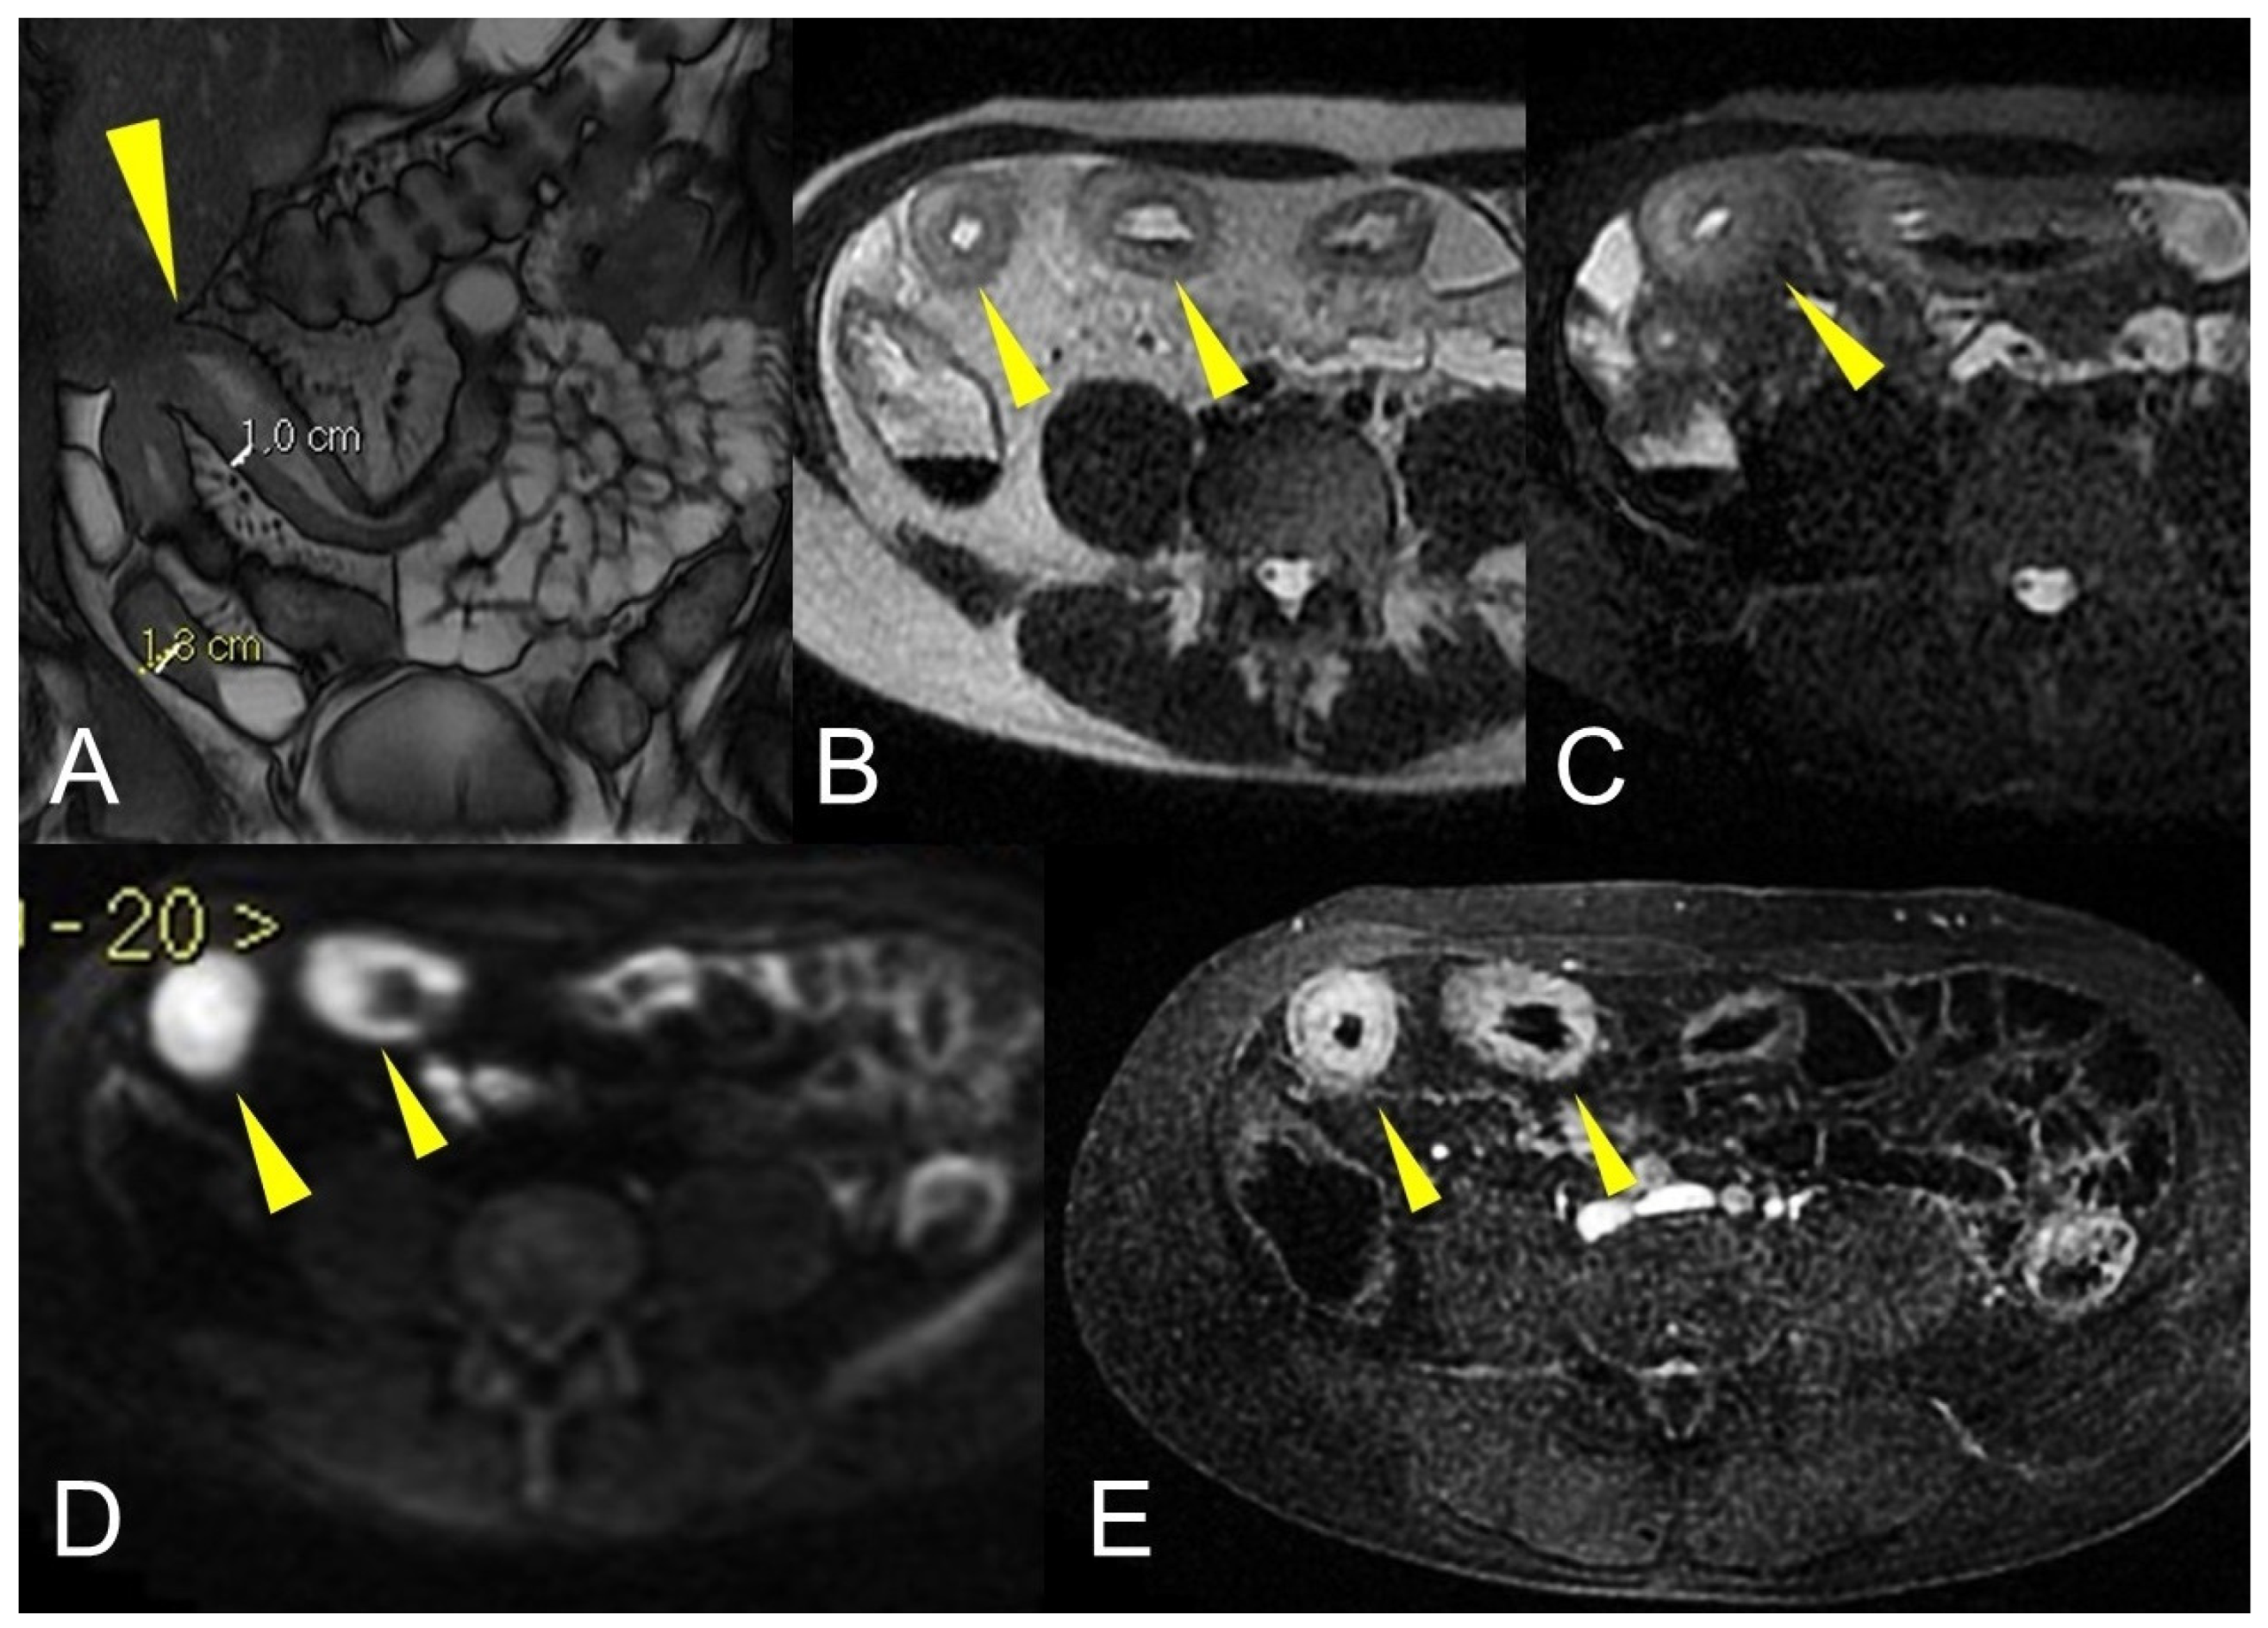

To assess the wall thickness, a good bowel distention is required (Figure 5A). Depending on the size, wall thickening should be subdivided as mild (3–5 mm), moderate (>5–9 mm), and severe (≥10 mm) [5]. However, asymmetric mass-like bowel wall thickening greater than 15 mm is atypical for Crohn’s disease, and cancer should be suspected. Intramural edema (Figure 5C) is typically investigated in fat-suppressed T2-weighted images where it appears as hyperintense intramural bowel. Ulcerations are consistent with a defect confined to the bowel wall, containing air or enteric intraluminal contrast that is focused in the inflamed bowel wall without extraluminal spreading [5,6]. The affected intestinal loops can present sacculation or pseudodiverticular extroversions of the antimesenteric side due to acute or chronic mesenteric border inflammation [5,6] (Figure 6). Intestinal strictures are defined as abnormal narrowing of bowel lumen with unequivocal upstream loop’s dilation. It is a common complication of CD and, according to the pathogenetic pathway, may be subdivided into fibrotic, inflammatory, and mixed types [6,7,8,9]. Important information in the radiological report should be the location, length, and dilatation’s size of the loops upstream to the stenosis (without upstream dilation if the lumen is <3 cm, mild upstream dilation if it is between 3–4 cm, and moderate to severe in upstream lumen >4 cm [6]. In upstream dilation greater than 4 cm, radiologists should report the presence of small bowel obstruction. Surgical treatment plays an important role in managing the CD’s stricture, especially when endoscopy is contraindicated (e.g., the intestinal tract is not endoscopically accessible or high risk of endoscopic dilatation) [9] (Figure 1 and Figure 2). An active inflammation may be recognized by restricted diffusion (Figure 5D); although this is a non-specific sign, it can be helpful when the bowel is inadequately distended [10]. Therefore, the use of DWI and ADC sequences must be performed by an experienced radiologist to contextualize the findings in the set of the multiparametric examination.

Figure 5.

Active inflammatory Crohn’s disease component revealed by MRE imaging. Coronal fast imaging employing steady-state acquisition (FIESTA) image (A) show mural thickening involving the terminal ileum (yellow arrowhead). Axial T2-weighted MRE image (B) of the same patient shows small bowel hyperintense wall thickening (yellow arrowheads) with matching parietal edema, restricted diffusion, and homogeneous enhancement, respectively in axial T2-weighted images with fat suppression ((C), yellow arrowheads), axial diffusion-weighted image ((D), yellow arrowheads), and contrast-enhanced fat-suppressed T1-weighted image ((E), yellow arrowheads).

In the presence of small bowel thickening, degree, type, and extension of wall thickening must be indicated in the report. Depending on the wall thickness, thickening can be mild (<1 cm), moderate (>1 cm and <2 cm), or marked (>2 cm) [29] (Figure 16A).

Figure 16.

Degree of wall thickening and type of involvement along bowel circumference. (A) Axial T2-weighted image shows mild thickening (<1 cm) of an ileal loop in the pelvis (arrow). (B) Axial T2-weighted image shows moderate symmetric thickening (>1 cm and <2 cm) of a small bowel loop (black arrow), supported by edema of the submucosal layer. (C) Axial T2-weighted image shows marked asymmetric thickening (>2 cm) of an ileal loop in the pelvis (arrows); the other side of the bowel wall is less thick (arrowheads).

Thickening throughout the intestinal loop circumference might be eccentric (asymmetric) or circumferential (symmetric) depending on the type of involvement (Figure 16B,C) [29,30]. According to the length of the pathological bowel tract, thickening can be focal, segmental, or diffuse. Bowel thickening is defined as focal when the pathological tract is shorter than 5 cm in length (Figure 17A); segmental thickening refers to 6–40 cm in length of thickened small bowel (Figure 17B), while it is considered diffuse when a large amount of small bowel loops (>40 cm) is affected (Figure 17C) [29,30]. After contrast-medium injection, various patterns of wall enhancement can be described: stratified, white, and gray [30]. Contrast enhancement is classified as stratified when there is hyperintensity of the inner layer (muco-sa), hypointensity of the intermediate layer (submucosa), and hyperintensity of the outer layer (muscle and serosa layers); this is caused by mucosal hyperemia and submucosal edema. If stratified contrast enhancement is associated to fat deposits in the submucosal layer, it is called “fatty halo” sign [30,31].